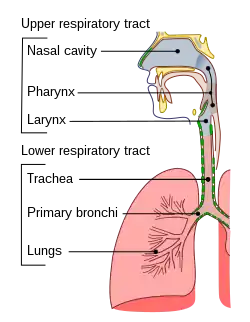

Pulmonary aspiration is the entry of material such as pharyngeal secretions, food or drink, or stomach contents from the oropharynx or gastrointestinal tract, into the larynx (voice box) and lower respiratory tract, the portions of the respiratory system from the trachea (windpipe) to the lungs. A person may inhale the material, or it may be delivered into the tracheobronchial tree during positive pressure ventilation. When pulmonary aspiration occurs during eating and drinking, the aspirated material is often colloquially referred to as "going down the wrong pipe".

In healthy people, aspiration of small quantities of material is common and rarely results in disease or injury. People with significant underlying disease or injury are at greater risk for developing respiratory complications following pulmonary aspiration, especially hospitalized patients, because of certain factors such as depressed level of consciousness and impaired airway defenses (gag reflex and respiratory tract antimicrobial defense system). The lumen of the right main bronchus is more vertical and slightly wider than that of the left, so aspirated material is more likely to end up in this bronchus or one of its subsequent bifurcations.

The location of abscesses caused by aspiration depends on the position one is in. If one is sitting or standing up, the aspirate ends up in the posterior basal segment of the right lower lobe. If one is on one's back, it goes to the superior segment of the right lower lobe. If one is lying on the right side, it goes to the posterior segment of the right upper lobe, or the posterior basal segment of the right upper lobe. If one is lying on the left, it goes to the lingula.